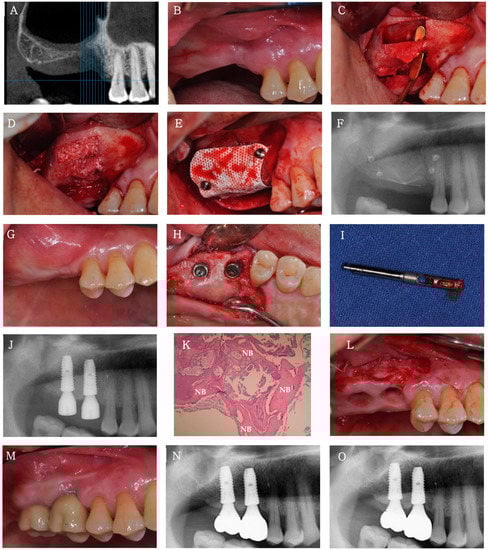

A 69 year old man visited the clinic for bone augmentation and implant placement in the 24–27 region. As a severely atrophic alveolar ridge was expected, vertical ridge augmentation was performed first using Bontree® mixed with whole blood and a titanium mesh (Jeil Medical, Seoul, Korea) prefabricated on a 3D-printed model. The first stage of implant surgery for 24, 26, and 27 was performed 6 months after ridge augmentation. High primary stability was achieved at the time of implant (Luna®, Shinhung Co., Seoul, Korea) placement, and sufficient buccal and lingual marginal bone width was confirmed. Four months after implantation, vestibular loss and a lack of buccal attached mucosa were observed with vertical bone loss. Therefore, an apically positioned flap was performed simultaneously with the second-stage implant surgery, followed by the application of an absorbable periodontal dressing (Reso-Pac®, Hager & Werken GmbH & Co., KG, Germany). The final prosthesis was provided approximately 6 months after implantation (Figure 5).

Figure 5.

Clinical case 2. (A,B) Clinical and radiographic views before vertical ridge augmentation in the 24, 26, and 27 regions. (C) Three-dimensional printed model of the severely atrophic posterior maxilla. (D) A prefabricated titanium mesh on the 3D-printed model before clinical application. (E) Buccal view after flap elevation. (F) Bontree® mixed with whole blood. A sticky bone graft with good manipulability is observed. (G) Buccal view of vertical ridge augmentation using Bontree® and a titanium mesh. (H) Radiograph after vertical ridge augmentation. (I) Occlusal view of 24, 26, and 27 implants placed 6 months after vertical ridge augmentation. (J) Radiograph after the first-stage implant surgery. (K) Occlusal view of the second-stage implant surgery using apically positioned flap and punching technique 4 months after implantation. (L) Radiograph after the second-stage implant surgery. (M,N) Clinical and radiographic views of the final prosthesis 6 months after implantation. (O) Radiograph at 1 year after loading.

A total of eight implants were placed in three patients who underwent sinus or alveolar ridge bone grafting with Bontree®. None of the patients had postoperative complications other than slight swelling at the surgical site. At 4 months after implantation, the ISQ values were >60 for all implants, indicating good implant stability (Table 1). All eight implants in all three patients were followed up for at least 12 months after functional loading, and the success rate, which was evaluated on the basis of the International Congress of Oral Implantologists Pisa Consensus implant health scale [], was 100% (Table 1). The radiograph at the 1 year follow-up showed integration of the implant with the regenerated bone and no bone loss or peri-implant radiolucency. No decrease in graft height was observed on any radiograph, and healthy peri-implant mucosa was established around all implants during the 1 year loading period.